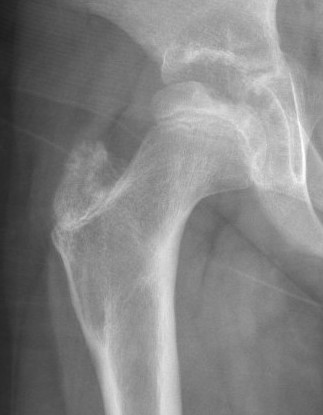

3. Reossification

Duration : 1.5 - 3 years

Pathologic Process

- starts at margins & progresses centrally

- eventually new areas coalesce & epiphysis regains normal strength & density

XRay

- Better defined shape

- Return of bone density